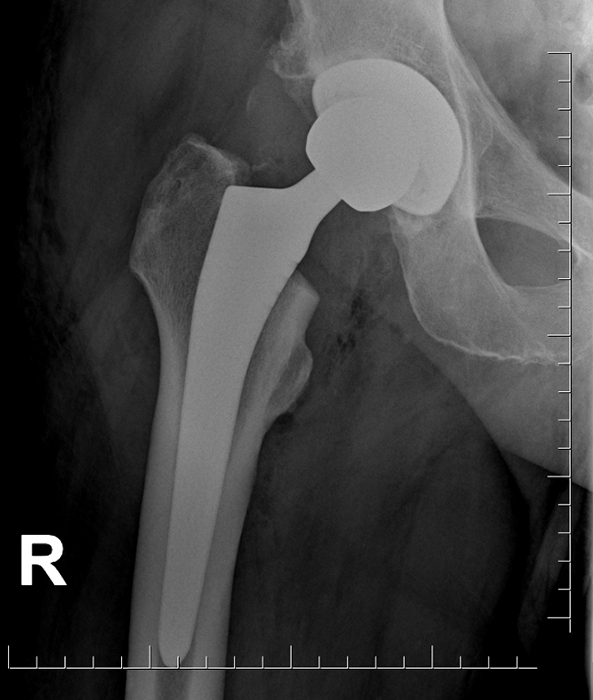

16 marca lekarze Ortopedyczno-Rehabilitacyjnego Szpitala Klinicznego im. Wiktora Degi Uniwersytetu Medycznego w Poznaniu wszczepili pierwszym pacjentom nowoczesne, produkowane w Polsce całkowite endoprotezy stawu biodrowego, który współtworzyli z inżynierami z firmy ChM z Białegostoku.

I tu przydało się wieloletnie doświadczenie poznańskich ortopedów, którzy pomogli inżynierom opracować nowoczesny implant. Jest on wykonany z tytanu, a dzięki specjalnym pokryciom jego powierzchni, po wszczepieniu do endoprotezy przyrasta kość. Całość zaprojektowano tak, by możliwe było implantowanie endoprotezy z zastosowaniem technik minimalnie inwazyjnych, które od lat stosowane są w poznańskiej klinice. Był to bardzo żmudny proces – w pierwszej kolejności przygotowano rysunki oraz trójwymiarowe modele komputerowe. Każdy implant i narzędzie stosowane w trakcie zabiegu było najpierw testowane wirtualnie – na ekranie komputera. Następnie ich prototypy przechodziły mordercze wręcz próby wytrzymałościowe przeprowadzane w akredytowanych laboratoriach w Polsce i Niemczech. Wspólne wysiłki medyków i inżynierów pozwoliły stworzyć nowoczesne implanty na światowym poziomie. Dzięki wielomiesięcznym, drobiazgowym przygotowaniom pierwsze zabiegi przebiegły sprawnie, a operowani pacjenci czują się dobrze i rozpoczęli już rehabilitację.